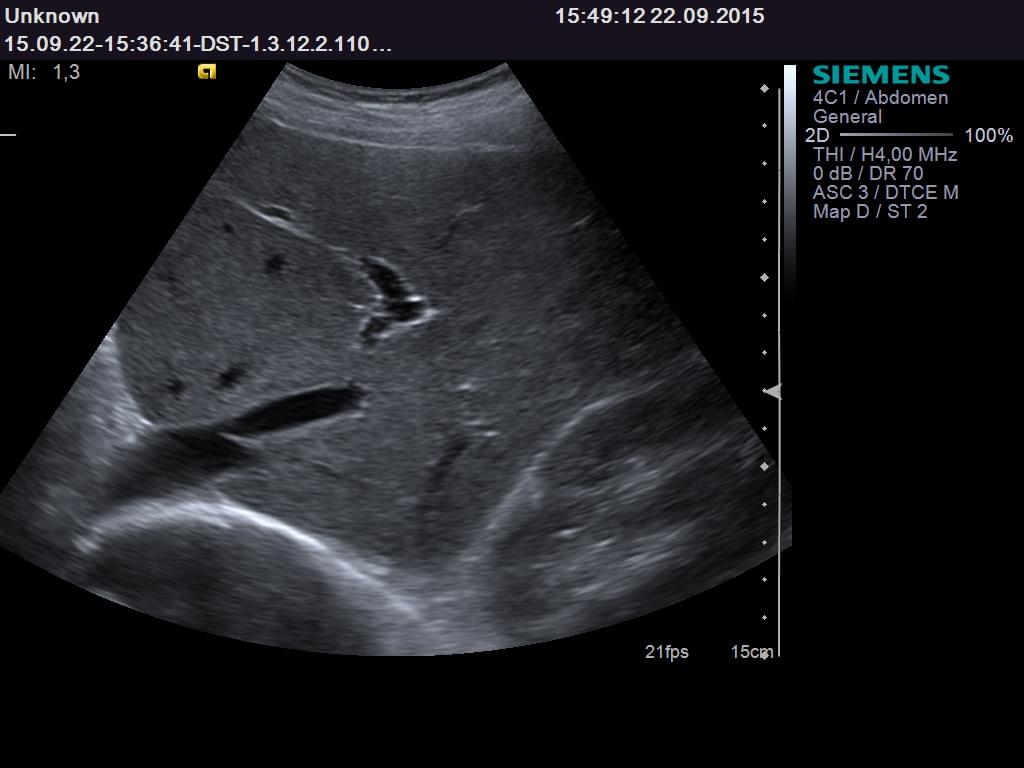

Завдяки цьому режиму ми можемо отримати надзвичайно чіткі та контрастні зображення. Ультразвукові хвилі, що відбиваються від внутрішніх структуру тіла, на екрані перетворюються у монохромну гаму. Чорно-біле зображення дозволяє лікарям розгледіти навіть найменші деталі, які можуть бути пропущені при інших методах діагностики.

Суть роботи УЗД полягає в застосуванні звукових хвиль високої частоти, які проникають в організм і відбиваються від різних органів та тканин. Ці відбиті хвилі сприймаються датчиком і перетворюються на візуальні зображення на екрані. У режимі сірої шкали кожна структура проявляється у відтінках сірого, що дає змогу виявити навіть найменші зміни в органах.